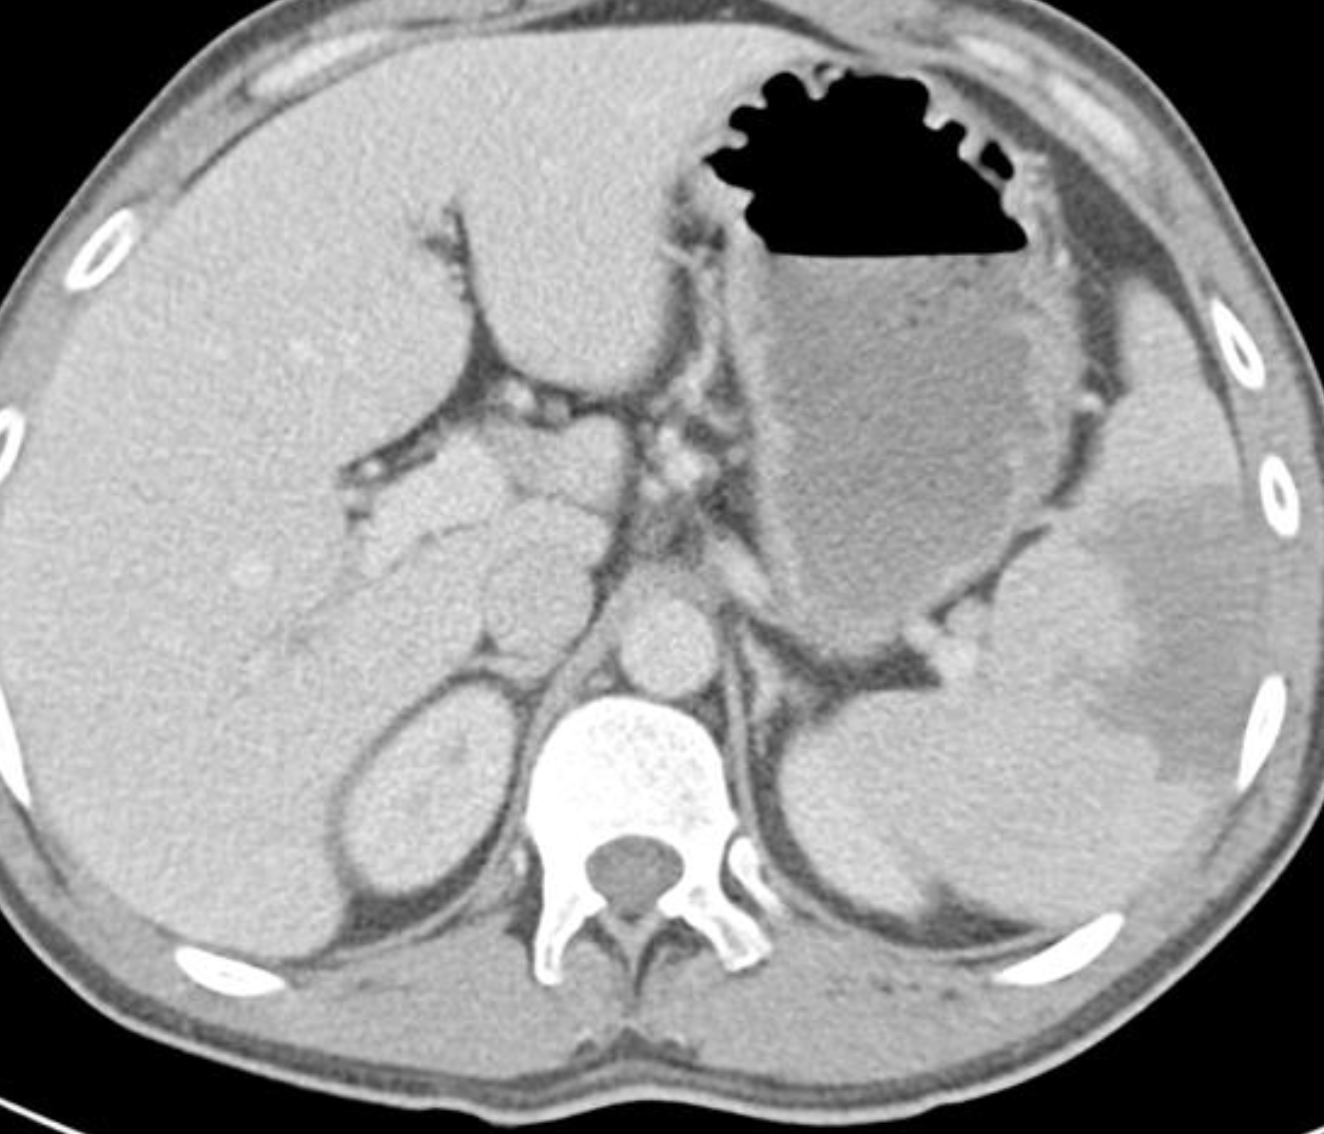

What are the causes of this condition?

The liver is at the upper limit of normal in size and her main portal vein is enlarged measuring 17 mm in diameter. The splenic vein is also enlarged. Focal fatty change is again demonstrated. No focal lesions. The remainder of the upper abdominal solid viscera are unremarkable, with no other infarcts identified. No lymph node enlargement and no focal osseous lesion.

Conclusion

Splenic infarcts is confirmed and presumably accounts of the patient’s presentation. The cause of the patient’s splenomegaly is uncertain, although the main portal vein and splenic vein do appear enlarged as does the liver raising the possibility of portal hypertension. Incidental adrenal adenoma.

Case Discussion

This case highlights the need to remember the differential of regional pain when assessing CT KUB for nephrolithiasis.